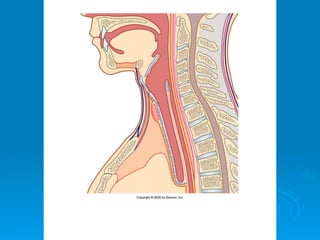

Hueso Hioides

Ø  No se articula con ningún otro

hueso.

Ø  Proporciona soporte a

músculos de la lengua y punto

de inserción a músculos que

participan en la deglución.

Ø  El hueso hioides también

ayuda a mantener la laringe

abierta todo el tiempo.

Ø  Lo ubicamos topográficamente

delante de C3